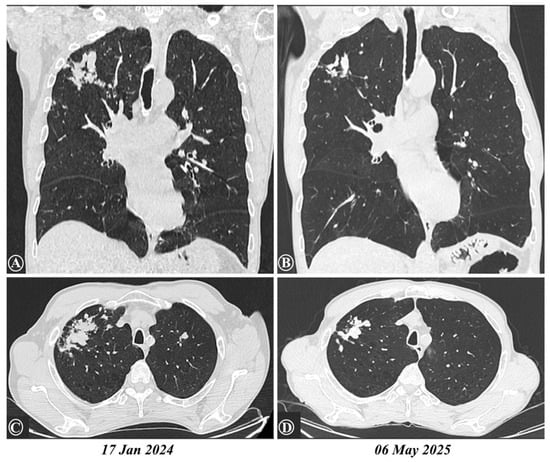

| Parameter (Normal Value) | 12 January 2023 | 18 December 2023 | 3 September 2024 | 6 May 2025 |

|---|---|---|---|---|

| BMI (kg/m2) | 20.9 | 19.59 | 21.22 | 21.79 |

| FEV1 (normal estimated 3.5 L) | 1.82 (52%) | - | 1.5 a (43%) | 1.86 a (53%) |

| CRP (0–5 mg/L) | 6.12 | 9.11 | 32.5 | 1.14 |

| ESR (3–10 mm/1 h) | 15 | 10 | 20 | 5 |

| Leucocytes (4–10 × 103/µL) | 6.2 | 10.31 | 17.19 | 5.85 |

| Eosinophils (0–0.7 × 103/µL) | 0.26 (3.7%) | 2.61 (29.9%) | 9.41 (54.7%) | 0 (0%) |

| Hemoglobin (14–17.2 g/dL) | 12.4 | 14.1 | 13.5 | 16 |

| IgE (0–100 UI/mL) | - | 2268.1 | 13,480.2 | >2500 b |

| Toxocara canis IgG (index < 0.9) | - | - | 3.892 | 4.168 |